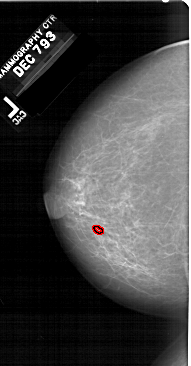

A_1513_1.RIGHT_MLO

RIGHT_MLO LINES 6511 PIXELS_PER_LINE 3391 BITS_PER_PIXEL 12 RESOLUTION 43.5 NON_OVERLAY

RIGHT_CC LINES 6286 PIXELS_PER_LINE 3301 BITS_PER_PIXEL 12 RESOLUTION 43.5 NON_OVERLAY